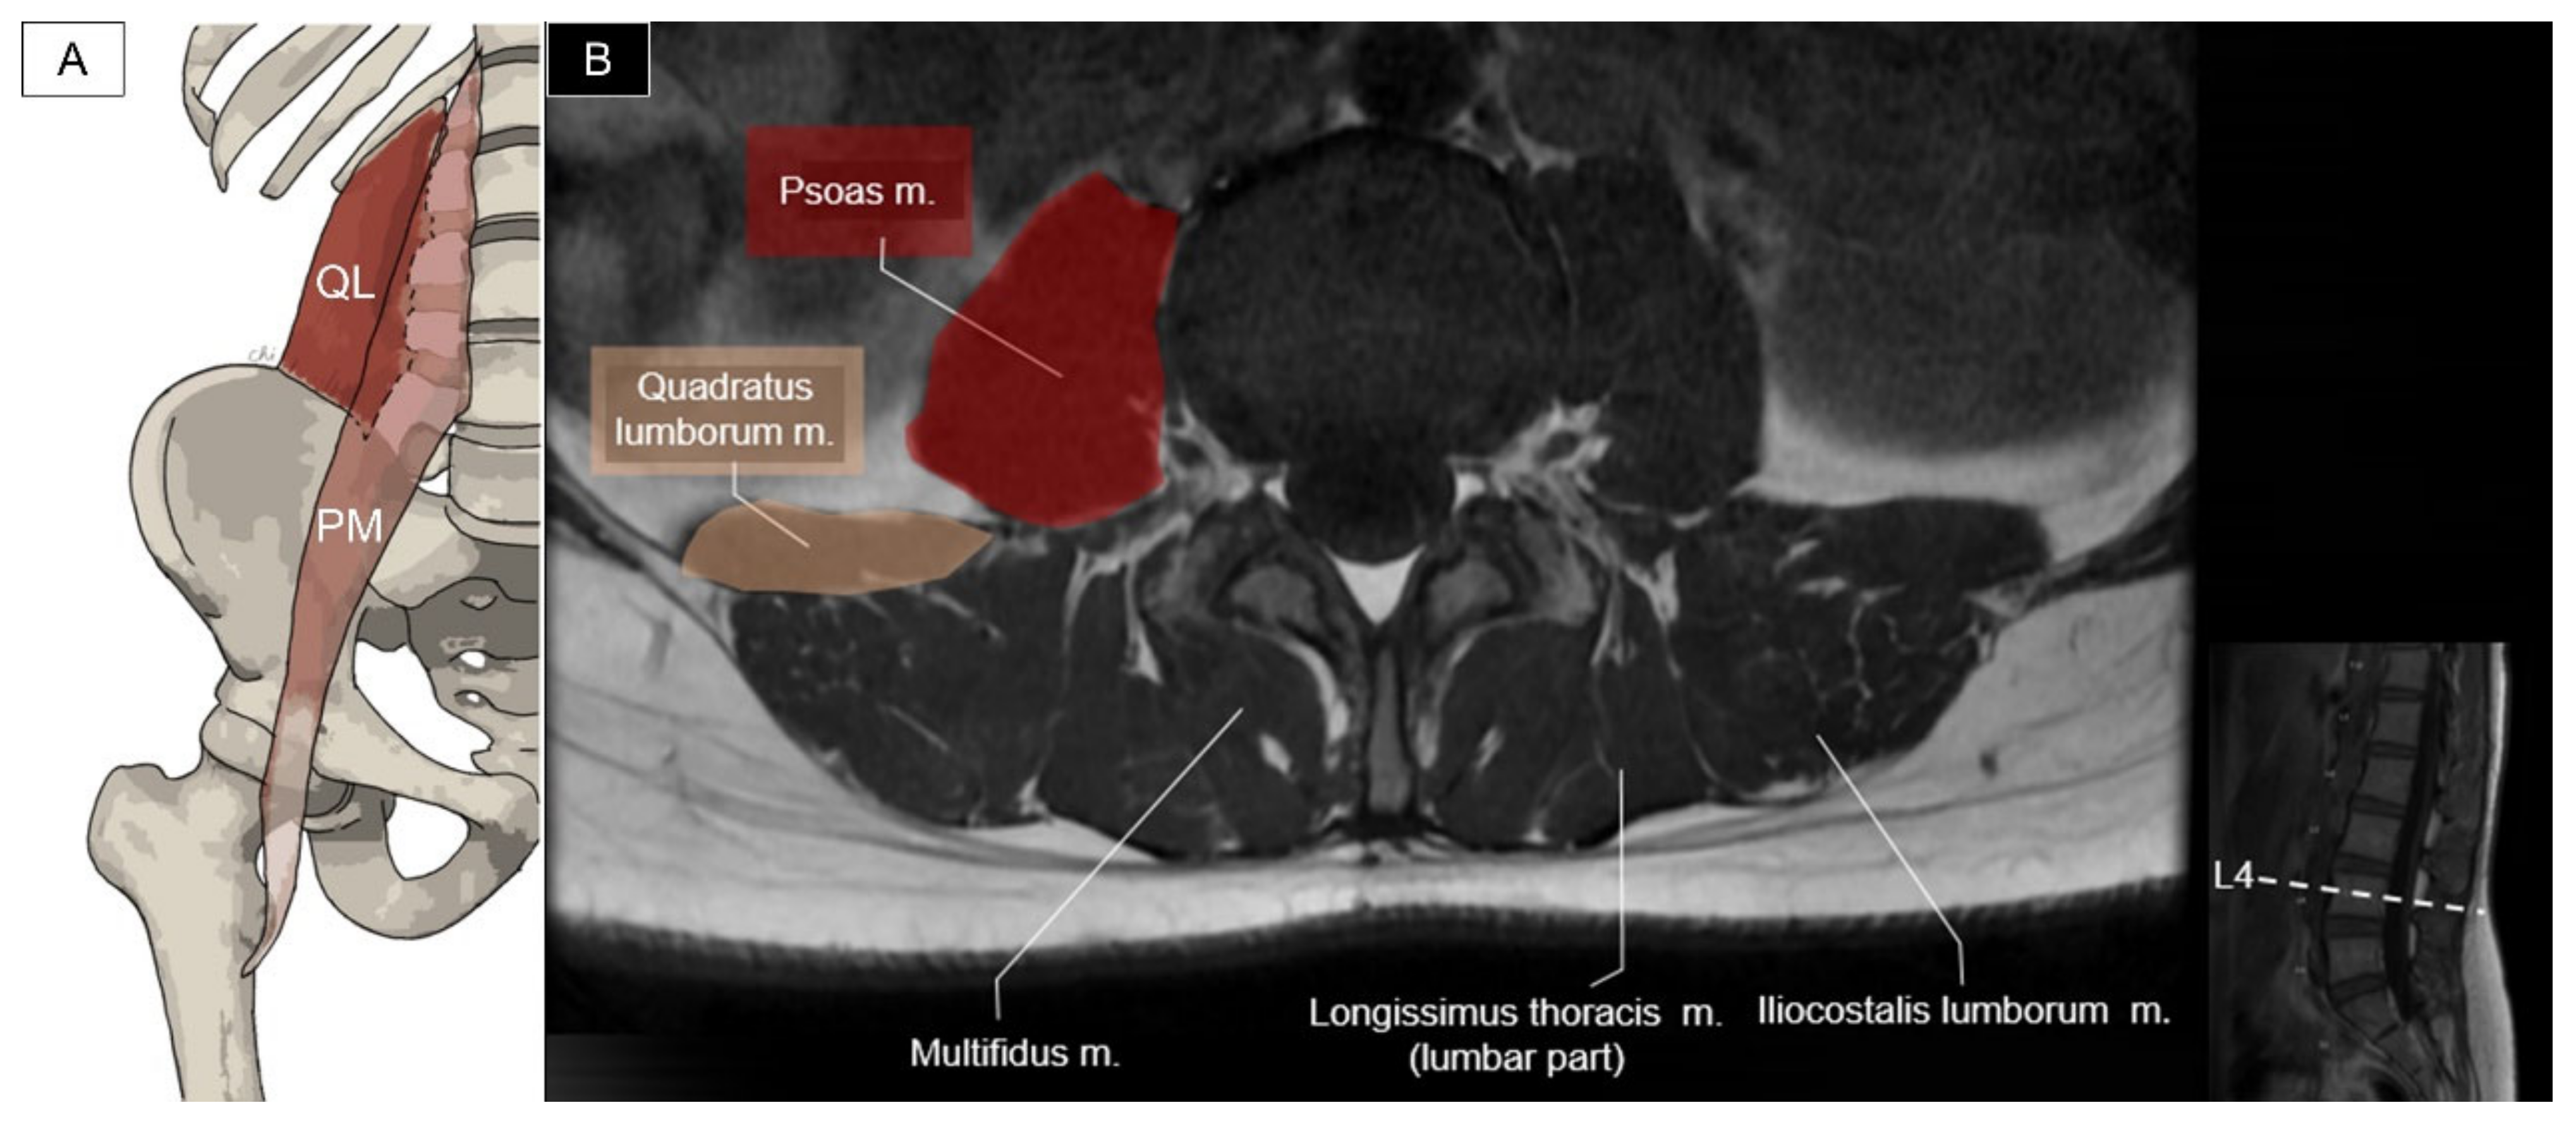

6.3. Quadratus Lumborum and Psoas Major

6.3.1. Anatomy

6.3.2. Sonographic Scanning

6.3.3. Clinical Relevance